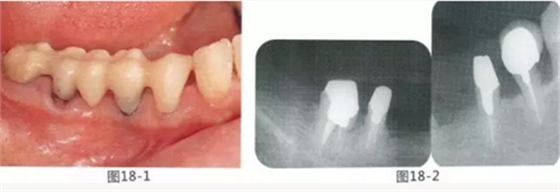

58歲女性,在修復(fù)治療前,為了去除牙周袋和獲得附著齦,頰側(cè)進行APF(齦瓣根尖側(cè)轉(zhuǎn)移),FGG(游離齦移植),舌側(cè)進行APF(齦瓣根尖側(cè)轉(zhuǎn)移)進行對應(yīng)的病例

圖18-1 右上4,5,6,6,7部位,初期治療結(jié)束時牙齦的狀態(tài)。

圖18-2 手術(shù)前同部位的口腔X光片。

圖18-4 去除臨時修復(fù)體后的頰側(cè)面照。在手術(shù)前去除右下5,6,7的金屬樁可以使手術(shù)更為方便。右下5,6部位基本看不到角化牙齦。

圖18-5 同部位的舌側(cè)面照片。角化牙齦較少,將牙槽嵴頂預(yù)測切開的話很有可能會沒有任何角化牙齦。